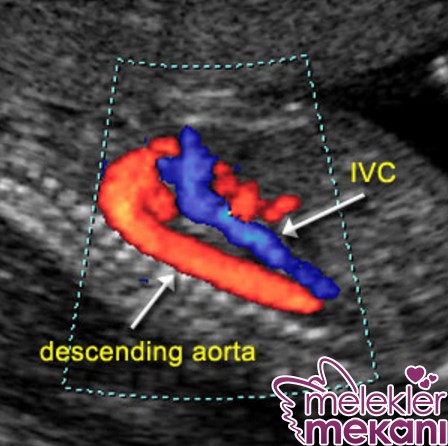

Практическое применение допплерографии маточной артерии